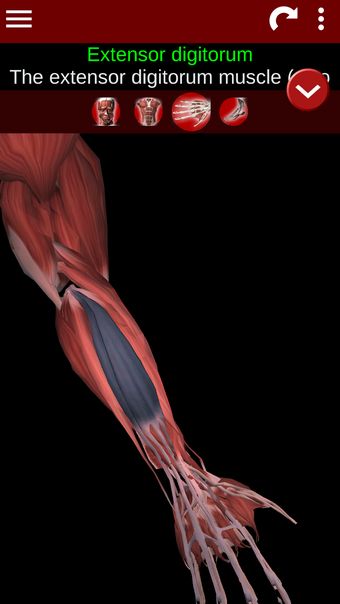

Esta herramienta educativa proporciona una descripción de cada músculo del cuerpo humano, así como un modelo tridimensional del sistema muscular. Con sólo tocar con el dedo, la aplicación revelará la información pertinente.

Los usuarios pueden hacer zoom sobre el músculo, así como elegir si ocultar o mostrar los datos. La orientación puede ser horizontal o vertical, según convenga más.